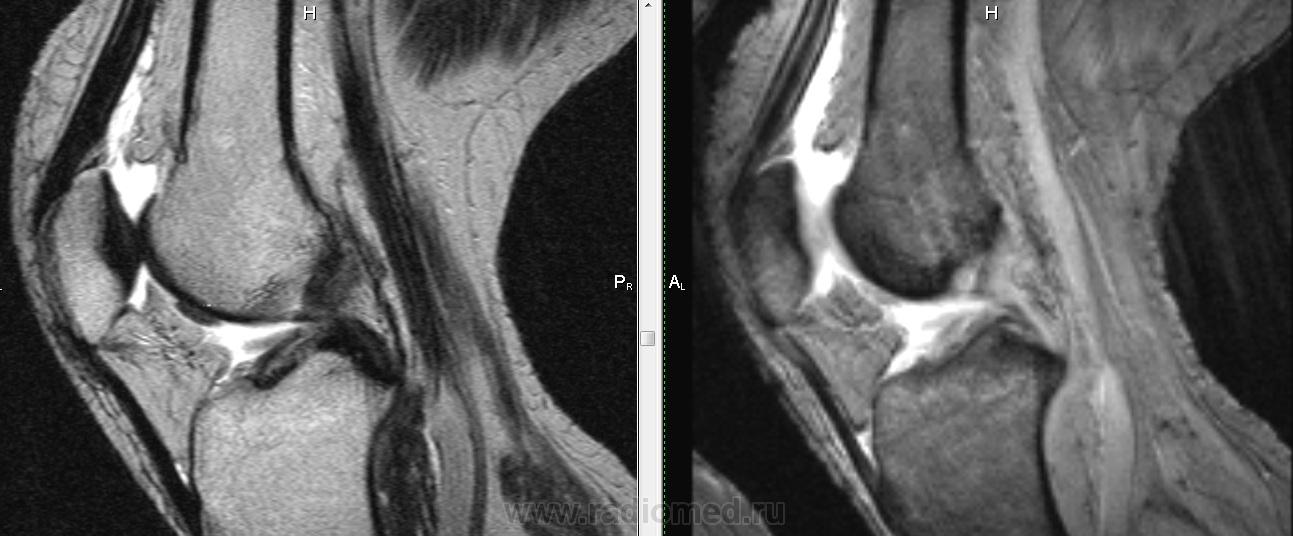

Падение с велосипеда. Вперед выступает фрагмент ПКС?

Не очень понятно, Михаил Александрович.Как-будто бы симптом "двойной  крестообразной связки", но не совсем похоже: при  этом  связка как-бы дугообразно идет.И мениски визуально вроде бы целы.Не может это быть фрагментом  переднего рога мениска?

Трудно сказать, на фрагмен мениска более похоже. Да и ПКС не отечная и внутренний мениск какой-то дефицитный. Если вопрос о цесостности ПКС обычно косая проекция выручает.

Думаю , тут фрагмент   переднего рога и части тела  латерального мениска ,  он(фрагмент) совсем  оторвался и уплыл кпереди .